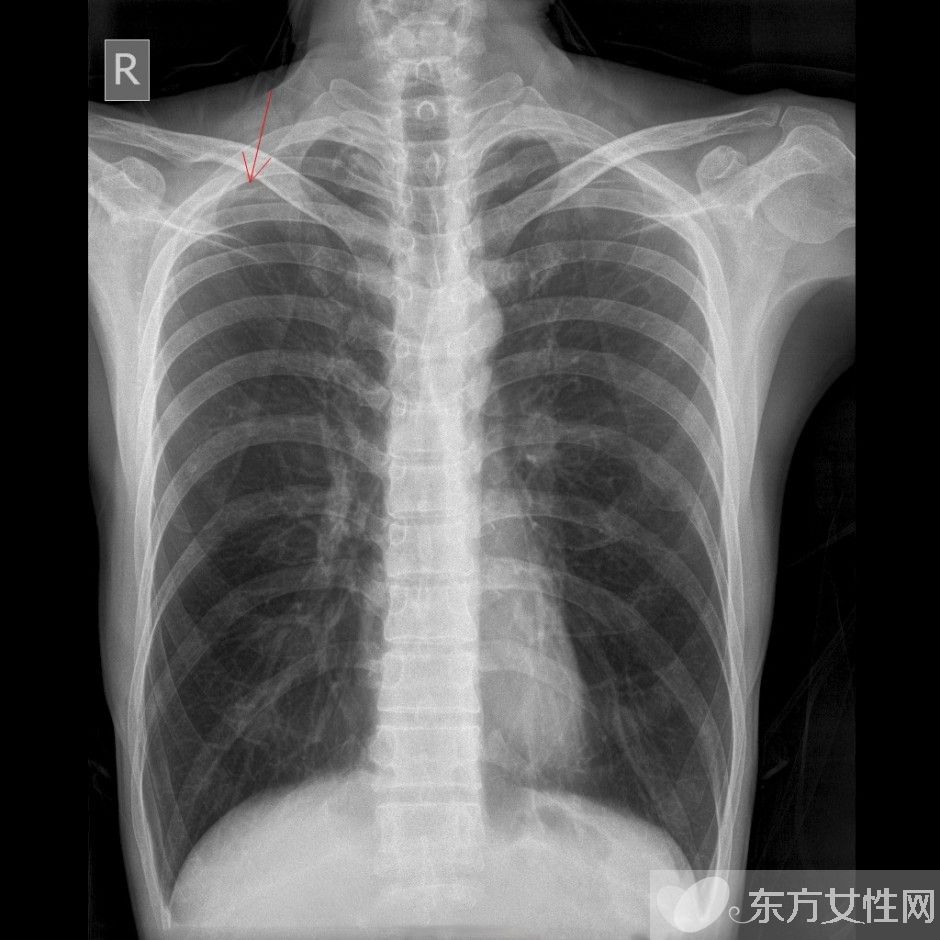

肺氣腫是指終末細(xì)支氣管遠(yuǎn)端(呼吸細(xì)支氣管,肺泡管、肺泡囊和肺泡)的氣道彈性減退,過(guò)度膨脹,充氣和肺容積增大或同時(shí)伴有氣道壁破壞的病理狀態(tài)。按其發(fā)病原因肺氣腫有如下幾種類型:老年性肺氣腫,代償性肺氣腫,間質(zhì)性肺氣腫,灶性肺氣腫,旁間隔性肺氣腫,阻塞性肺氣腫。

肺氣腫會(huì)傳染嗎?

北京治肺氣腫的專業(yè)醫(yī)院專家介紹,肺氣腫指的是人體的終末細(xì)支氣管遠(yuǎn)端,包括有肺泡管、呼吸細(xì)支氣管、肺泡囊和肺泡等,這些氣道的彈性衰弱,膨脹過(guò)度、充氣以及肺容積加大,或者合并氣道壁破壞的病狀。肺氣腫的分型有很多種,但是疾病是否具有傳染性還是要看其致病因素是什么。